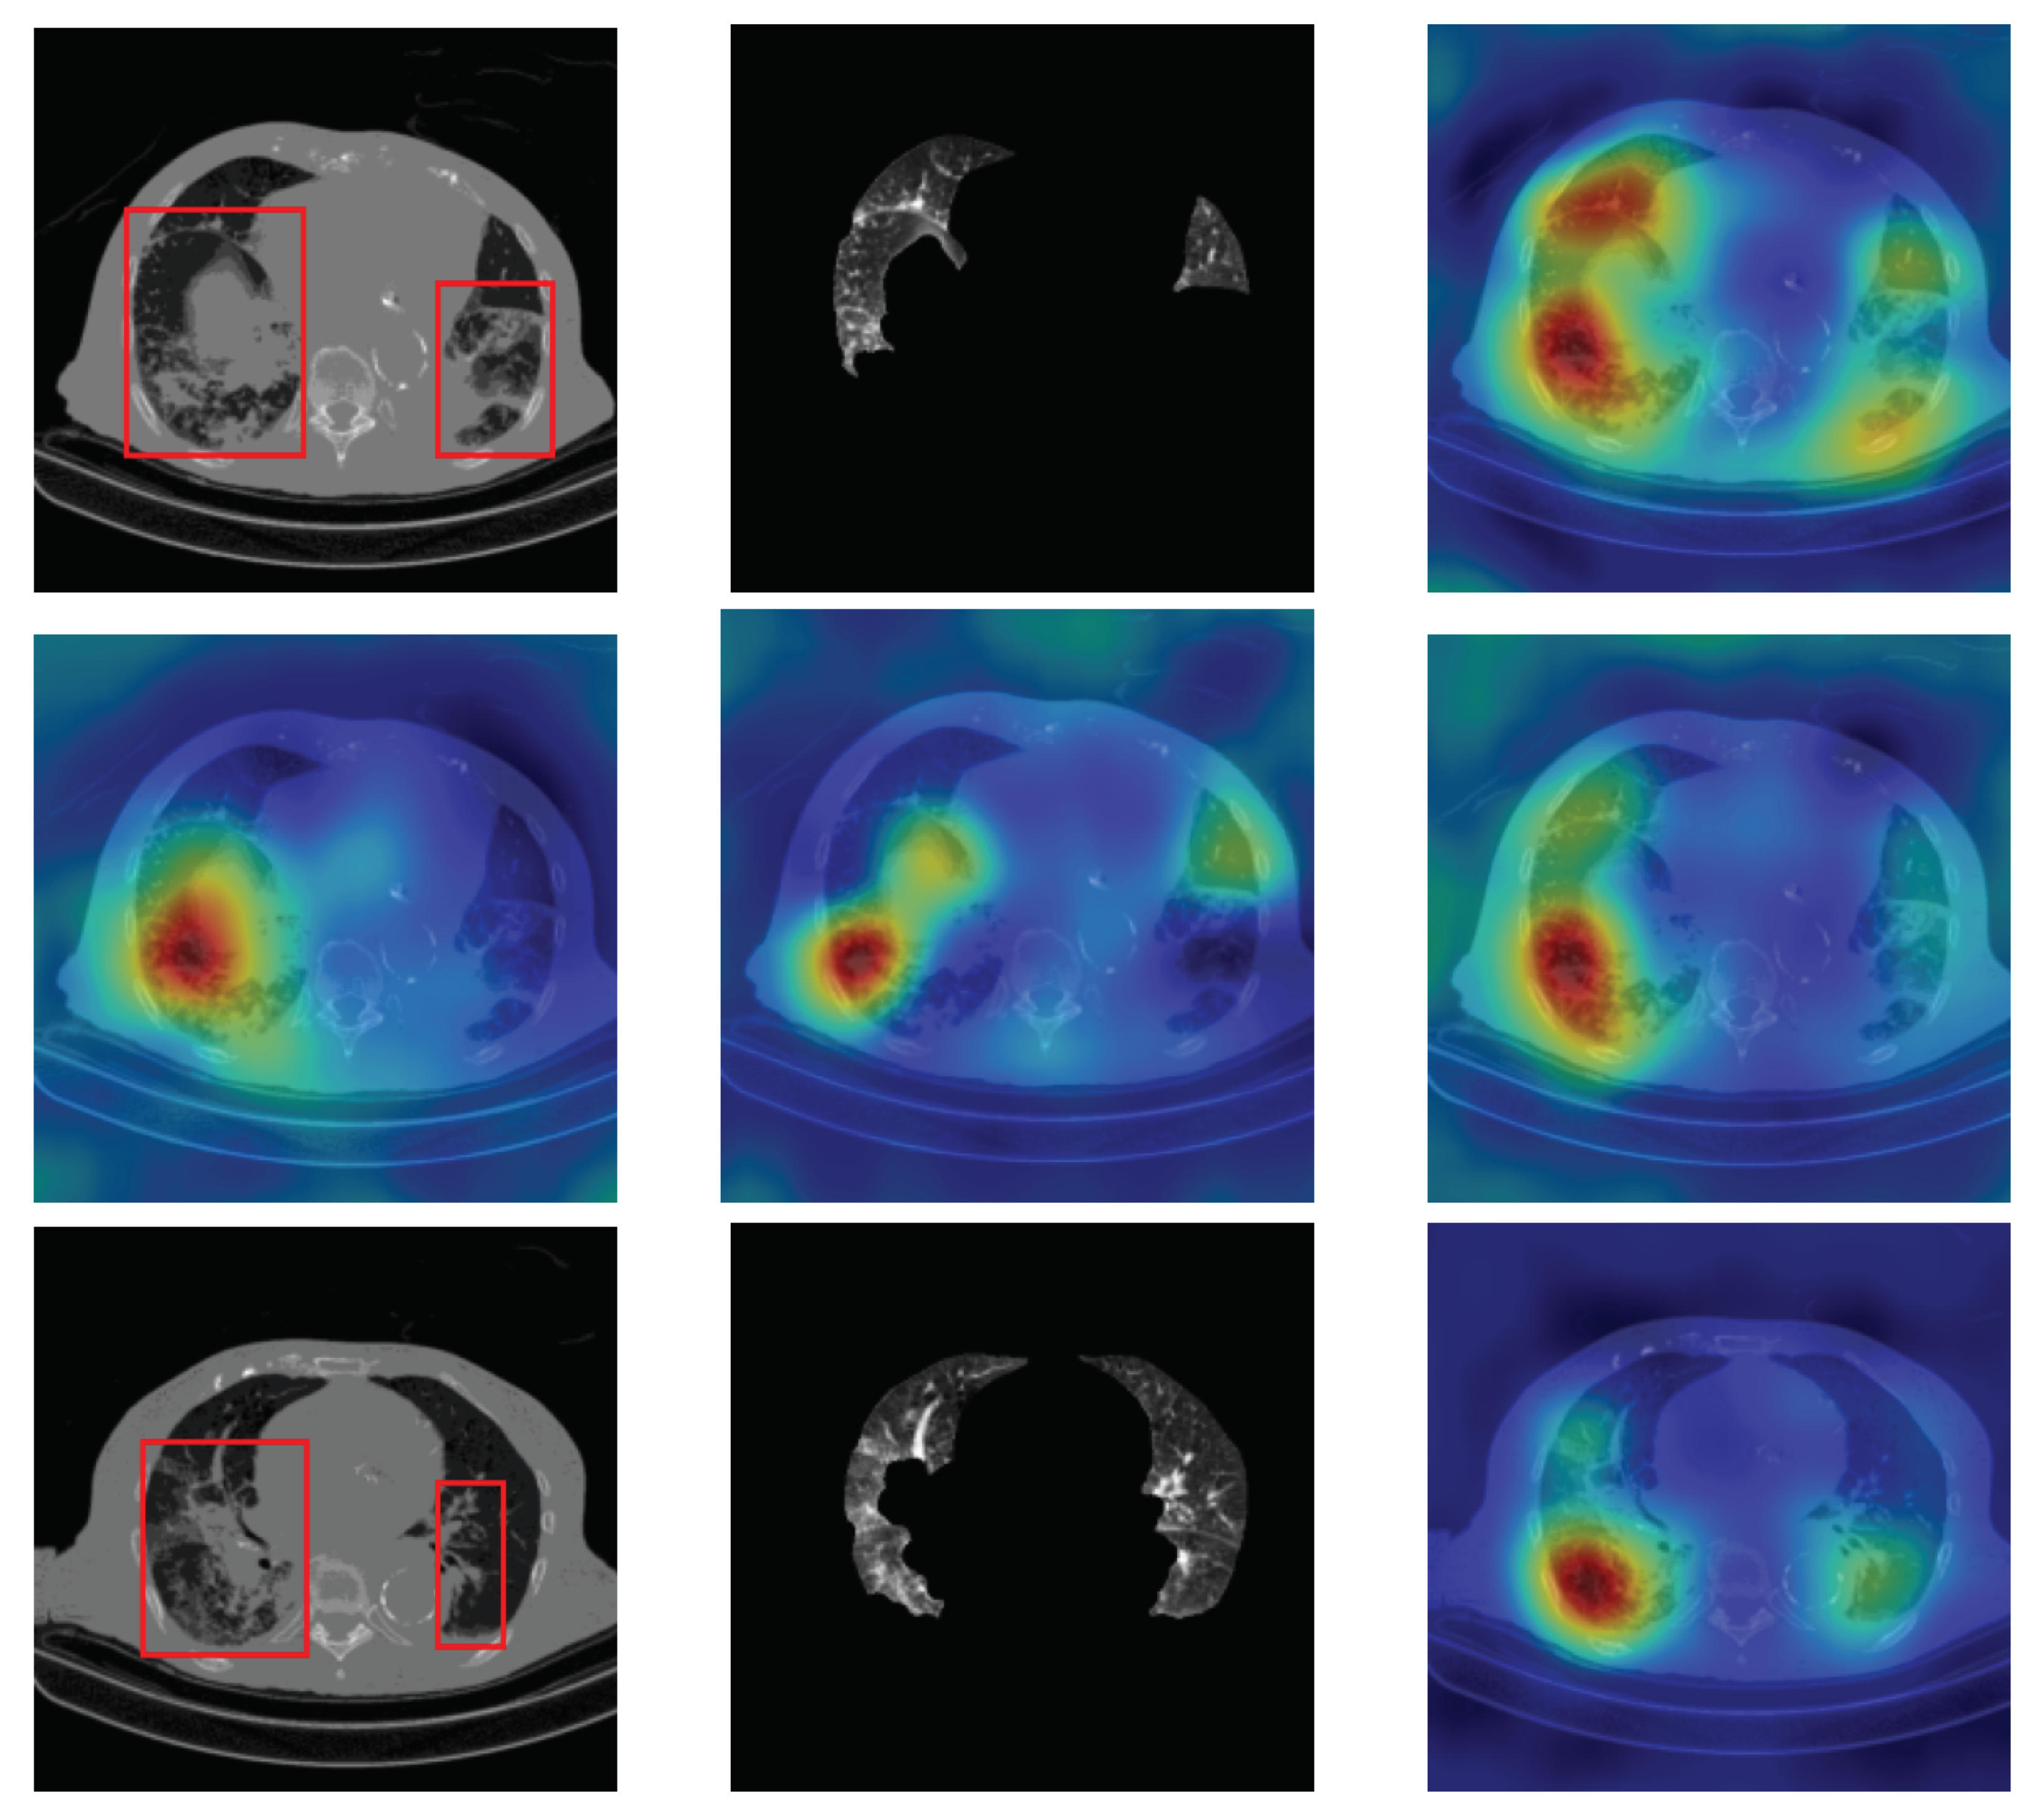

4.5. Heat Map

To have more intuition about the most important lung regions that the CNN architectures consider to classify the slice images, we used the randomized input sampling for explanations (RISE) approach [37]. Figure 13, Figure 14 and Figure 15 consist of two heat map examples of COVID-19, Cap, and normal cases, respectively. In the first example from Figure 13, we notice that despite the lung segmentation being not fully correct (it misses a considerable part of the infected region), the four CNN architectures gave more importance to the infected regions and to the lung regions in general. In the second example from Figure 13, we observe that the lung lobes were precisely segmented, and the heat maps of the four CNN architectures were well defined the infected regions, especially the Wide-Resnet-50 architecture. From both Cap examples in Figure 14, we notice that despite the lung segmentation missing considerable infected parts as well as the lung lobe regions, the heat maps of all CNN architectures give more importance to the infected region and to the lung lobes in general. This proves that the trained CNN architecture is able to define the regions of interest even when the lung lobes segmentation is not good. For the normal slice examples in Figure 15, the trained CNN architectures gave more importance to the lung lobes, especially the lower region, since the infection usually occurs there. The heat maps of COVID-19, Cap, and normal cases prove that the CNN architectures learned precisely where to look to identify the infection from the slice images.

Figure 13.

RISE heat map examples of COVID-19 slice images using the trained multi-tasks CNN architectures (ResneXt-50, Densenet-161, Inception-v3, and Wide-Resnet-50). The first example is shown in the first two rows, where the images represent the input slice image and segmented lung lobes results, followed by the heat maps of ResneXt-50, Densenet-161, Inception-v3, and Wide-Resnet-50, respectively. The second example is in rows 3 and 4.